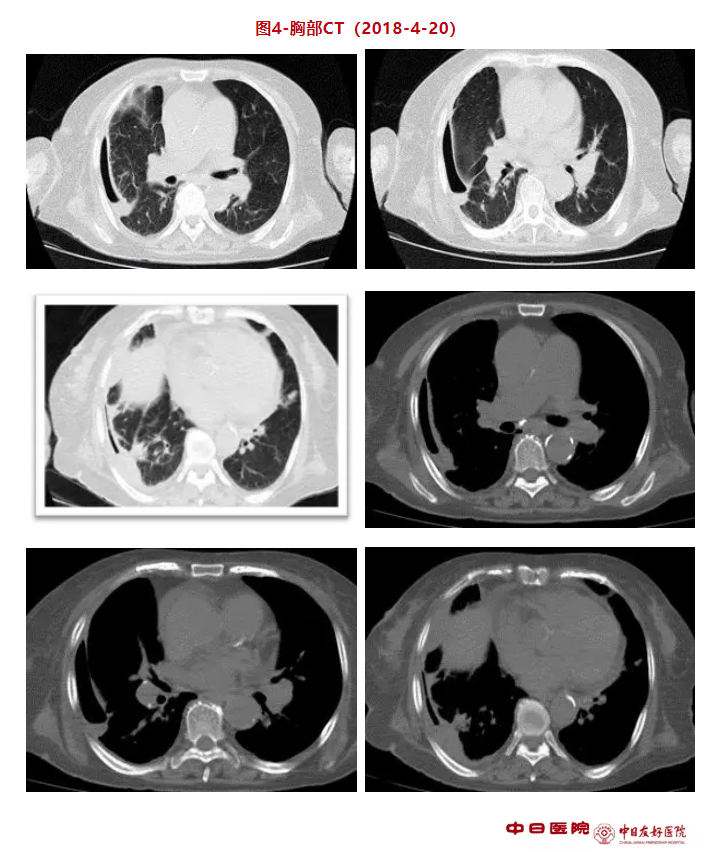

复查胸部CT(图4)示:目前肺内散在炎性病变,右侧胸膜增厚粘连,胸腔内积气积液。CTPA(图5)示:双肺动脉多发肺栓塞,肺动脉瓣略增厚,右侧液气胸,右侧胸膜增厚。经食道超声心动图示:心脏彩超:肺动脉瓣异常回声附着(41mm*7mm),血栓?赘生物?右心扩大、左房增大,室间隔增厚,主动脉硬化并反流(少量),三尖瓣反流(轻度),主肺动脉增宽,升主动脉增宽,肺动脉高压,心包积液(少量)。考虑肺动脉瓣感染性心内膜炎(IE)诊断明确。因患者为真菌性IE,且栓子直径大于10mm,合并肺栓塞,有手术指征,但患者家属因经济问题拒绝手术。之后更改为伏立康唑片 200mg bid治疗,患者体温大致正常,氧合好转,之后出院。